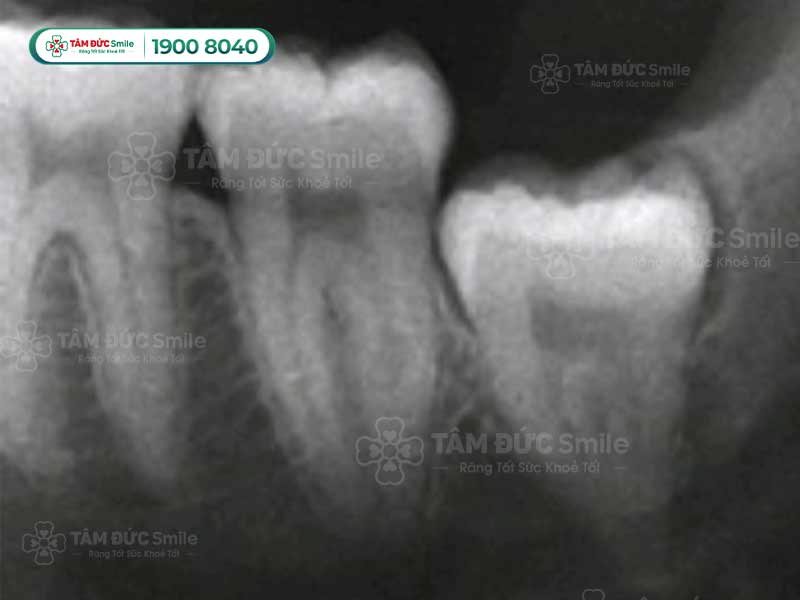

2.1.1. Răng khôn mọc lệch, mọc ngang

Người trưởng thành có cơ hàm, răng và nướu đã phát triển hoàn thiện. Răng số 8 mọc cuối cùng không còn đủ chỗ để trồi lên, phần lợi cứng dẫn tới mọc lệch hàng, mọc đâm ngang vào răng số 7.

Các trường răng khôn mọc lệch, đâm chéo, ngang các bác sĩ đều khuyên nhổ bỏ. Răng mọc không thẳng tác động xấu tới răng còn lại, khiến răng mẻ vỡ, mòn men răng và làm chúng ta đau nhức. Nếu cả 4 chiếc răng số 8 đều mọc lệch, dẫn tới hàm răng mất cân đối ảnh hưởng tới khớp cắn nghiêm trọng.